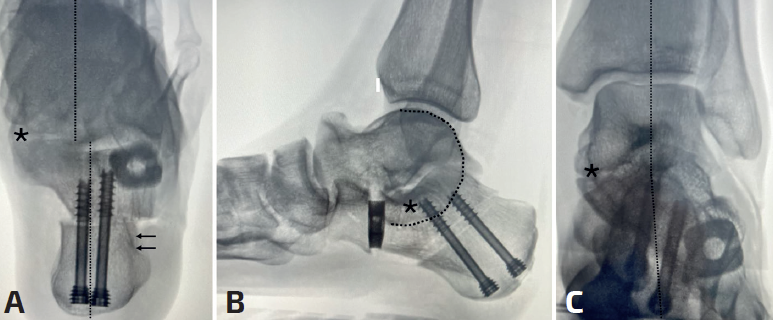

En caso de deformidad predominante en el plano coronal en valgo seleccionaremos la osteotomía de deslizamiento medial del calcáneo para medializar el vector vertical del tendón de Aquiles y aumentar su capacidad varizante para disminuir el estrés en las partes blandas mediales. La realizaremos del mismo modo que en el pie plano flexible, intentando alojar el eje del calcáneo debajo de la tibia (Figura 2), visualizado en una proyección axial en carga simulada, trasladando entre 10 y 15 mm. Si bien, en caso de coaliciones óseas talocalcáneas y rigidez subtalar, es frecuente no observar corrección del astrágalo en el perfil sagital, aunque sí corrección del valgo clínico y en proyección de Saltzman (ya que el valgo se corrige a nivel extraarticular).

Si ambas deformidades están presentes en un grado acusado o si al corregir una de ellas se observa una deformidad residual importante, la elección será combinar ambos tipos de osteotomías (Figura 2). Seguimos los mismos criterios de apertura que en el pie plano flexible, intentando no sobrepasar los 8 mm en adultos para evitar problemas en la calcaneocuboidea(10). En caso de persistir el valgo tras esta osteotomía o si para corregir necesitamos abrir una cuña de más de 1 cm, optaremos por realizar una doble osteotomía, añadiendo una traslación medial del calcáneo.